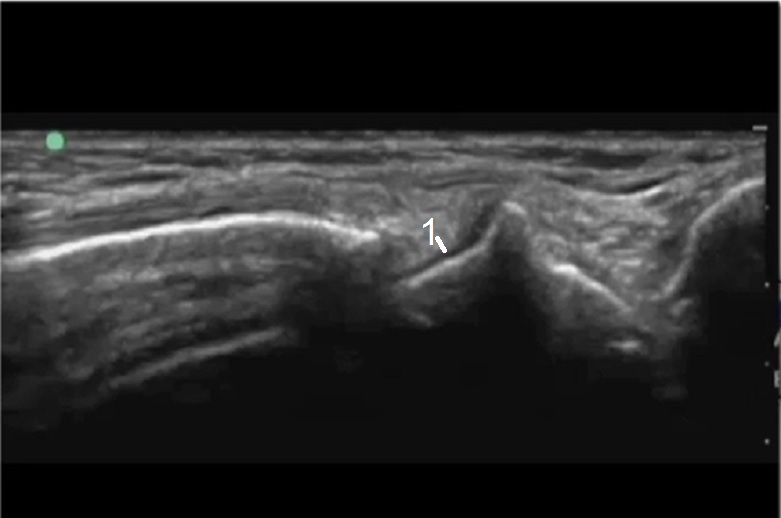

Wrist Radioscaphoid Recess Injection 2 Image

Articular Hyaline Cartilage (target for injection)